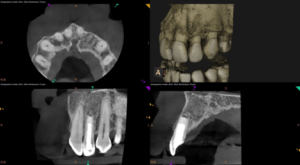

After 11 months, we’re thrilled to report significant improvements:

- Resolution of the apical lesion

- Acceptable healing around the root tip

- No tenderness or discomfort

While the outcome isn’t perfect, it’s a remarkable success given the tooth’s history and condition.